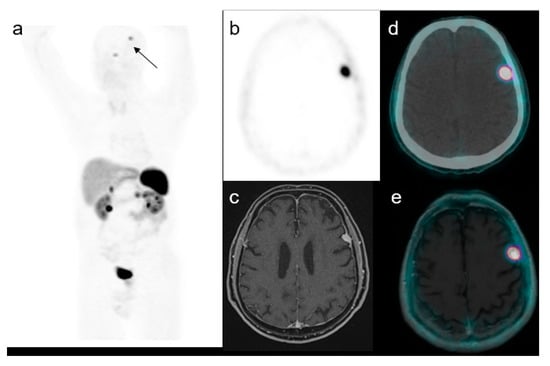

3. Results